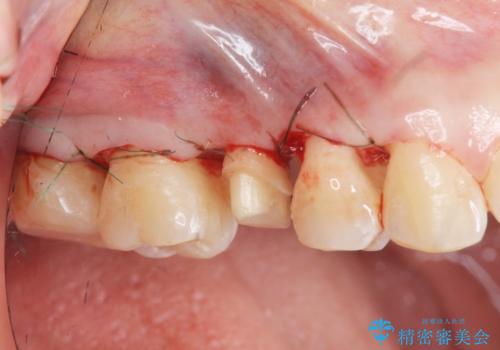

放置した虫歯を外科を行い抜歯を回避

- 放置していた虫歯が欠け、いよいよ怖くなり治療を希望され来院されました。

虫歯は、その進行度によりさまざまな治療法が提案されますが、

エナメル質・象牙質に限局する虫歯 →インレー修復

歯の神経に達する虫歯 →根管治療 クラウン補綴

歯ぐきよりも深い虫歯 →歯周外科による歯周環境の整備

を適宜行うことで良好な結果を得ることができます。

症状に応じて適切な処置を行ったことで、抜歯を回避し良好な結果を得ることができました。